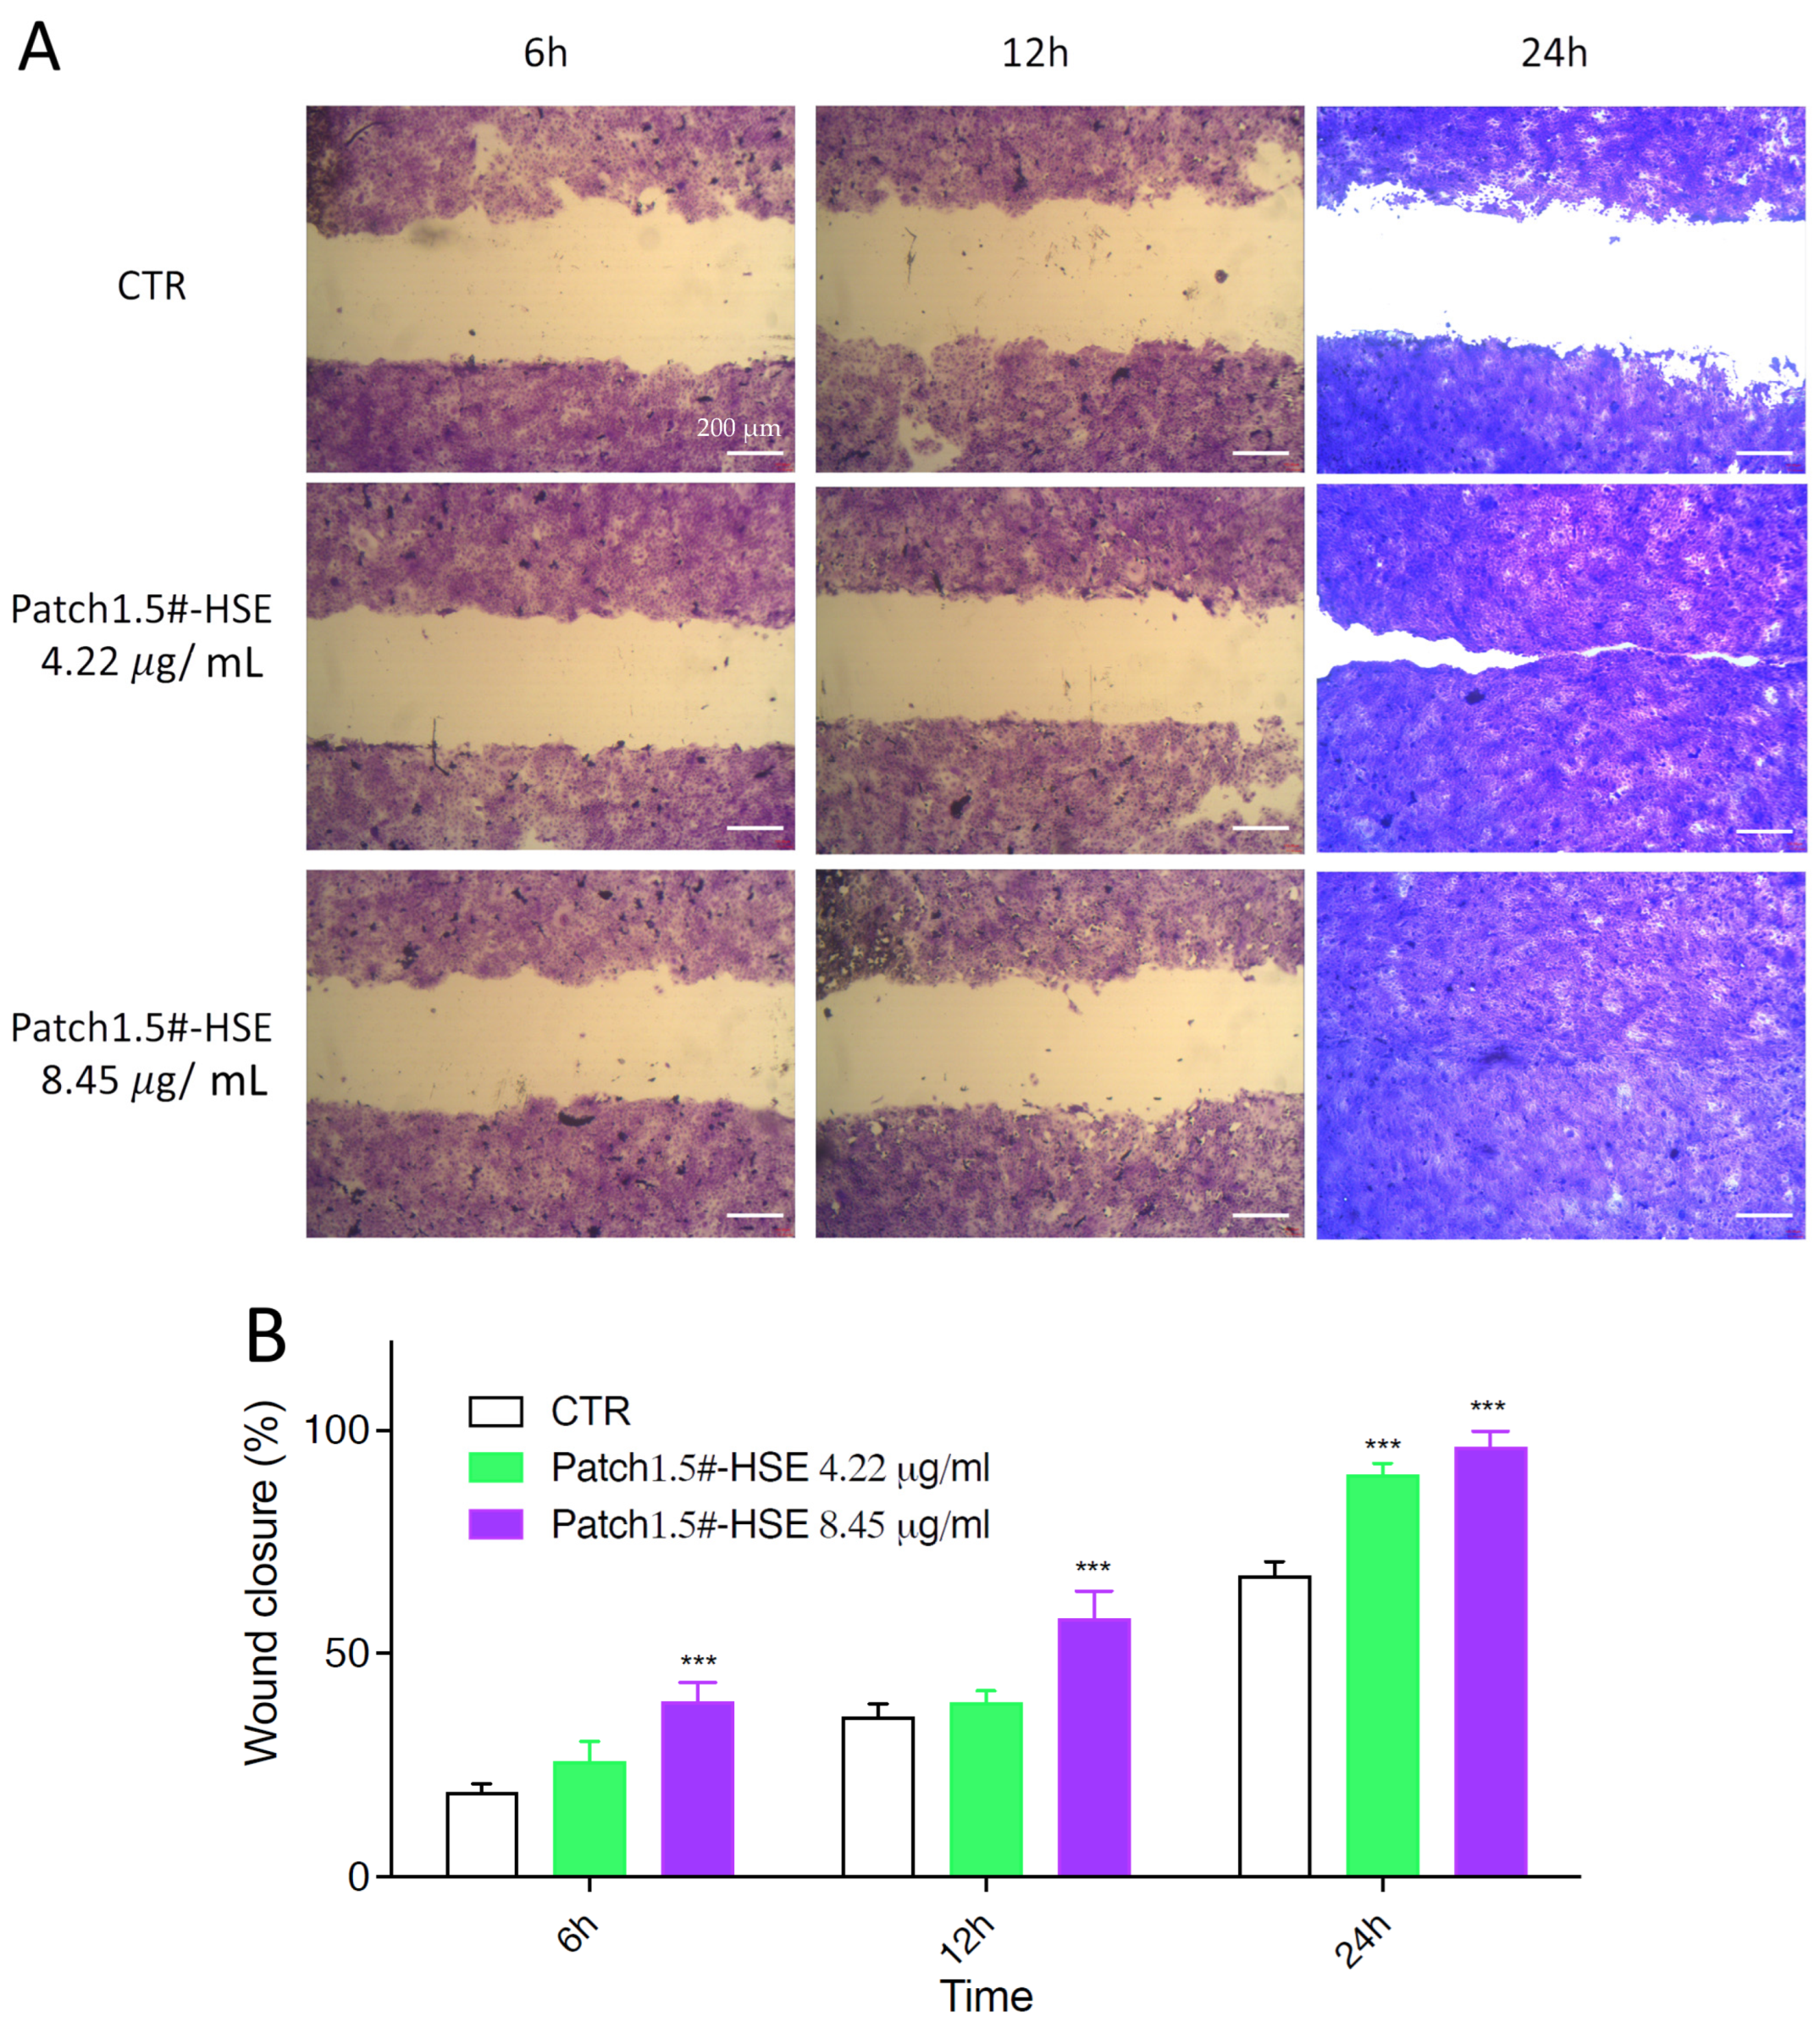

3.6.4. In Vitro Wound Healing Capacity